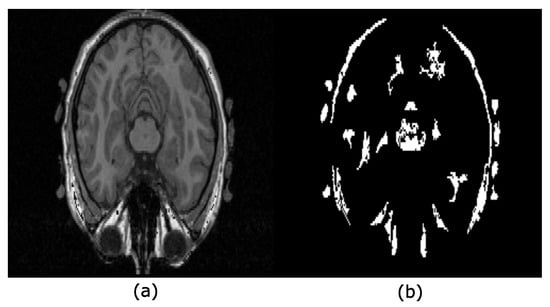

4.1. Brain Extraction Based on the Maximum Hyperconnected Function

4.2. Brain Extraction Based on Hyperconnected Functions and Lower Leveling